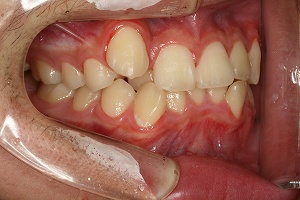

歯並びが気になるということで相談に来られました。非抜歯で矯正をすることができる状況でしたので、治療をすすめました。

叢生がひどく かみ合わせも浅かったために、苦労しました。